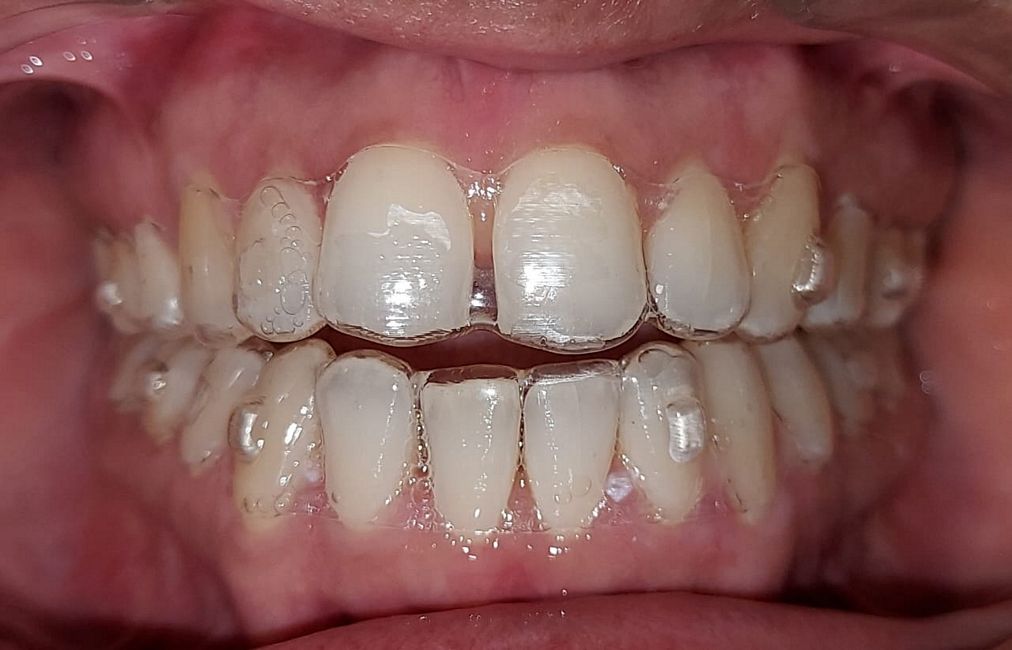

Case No: 23

Malocclusion Type: Class I Malocclusion.

Mechanics: MBT Mechanics.

Treatment: Class I Malocclusion with crowding in upper and lower anteriors treated by Non-extraction method.